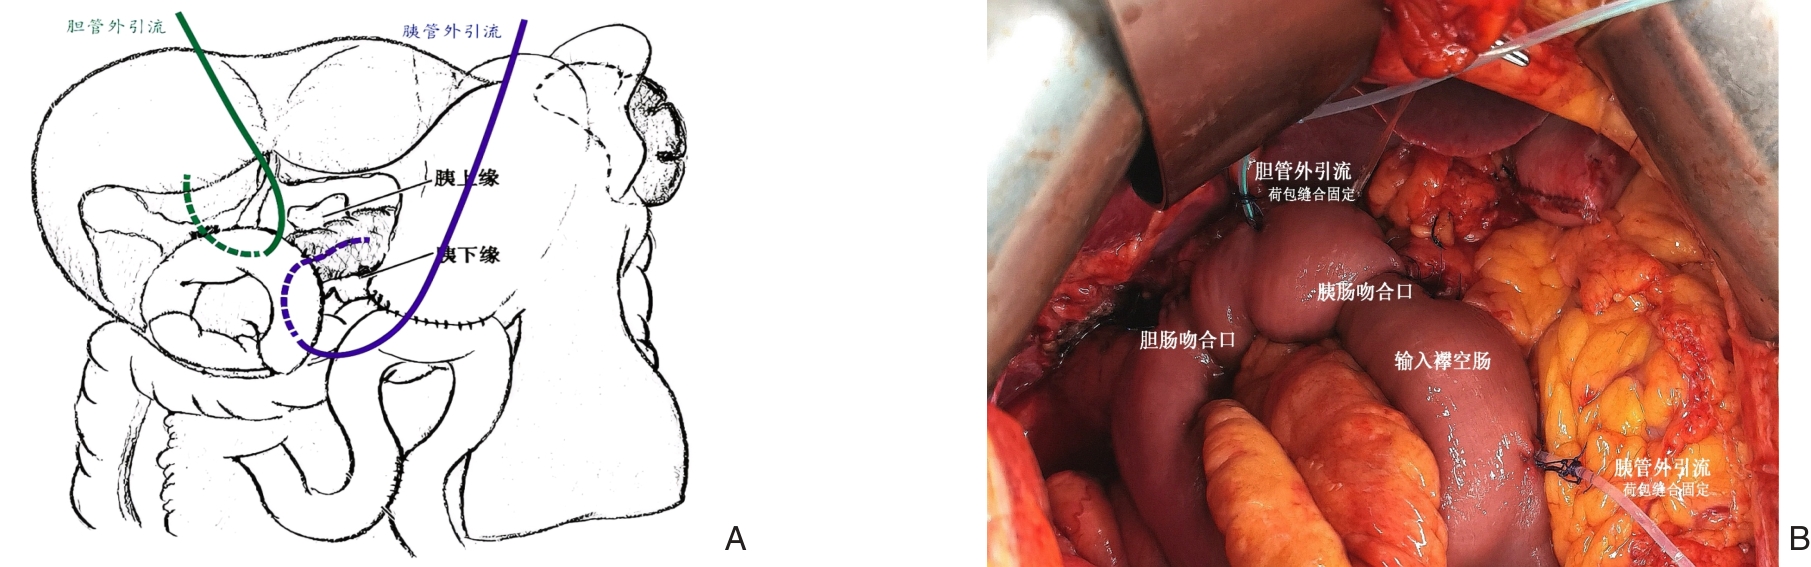

摘要:胰十二指肠切除术是胰腺外科风险最高、并发症最复杂的手术之一,其中临床相关胰瘘仍是影响术后恢复与预后的关键问题。近年来的研究显示,仅依靠改变胰肠吻合方式难以持续降低胰瘘发生率。复旦大学附属中山医院胰腺外科提出并研发的“预防性胆-胰双分流系统”,通过术中同步引流胆汁与胰液,实现“减压+分隔”的双重保护机制,旨在从源头上阻断胰液被激活的病理链条,降低吻合口并发症发生风险。本文系统阐述了该系统的设计原理、临床应用与早期试验结果,并结合多中心随机对照研究进展,探讨其适应证界定、术中操作要点、外引流管理及患者依从性等关键环节。同时,文章展望了基于风险分层、智能引流、抗菌管理和材料学创新的未来发展方向。作为一种兼具理念创新与工程转化的防瘘策略,预防性胆-胰双分流系统有望成为防控胰十二指肠切除术后并发症的新范式。